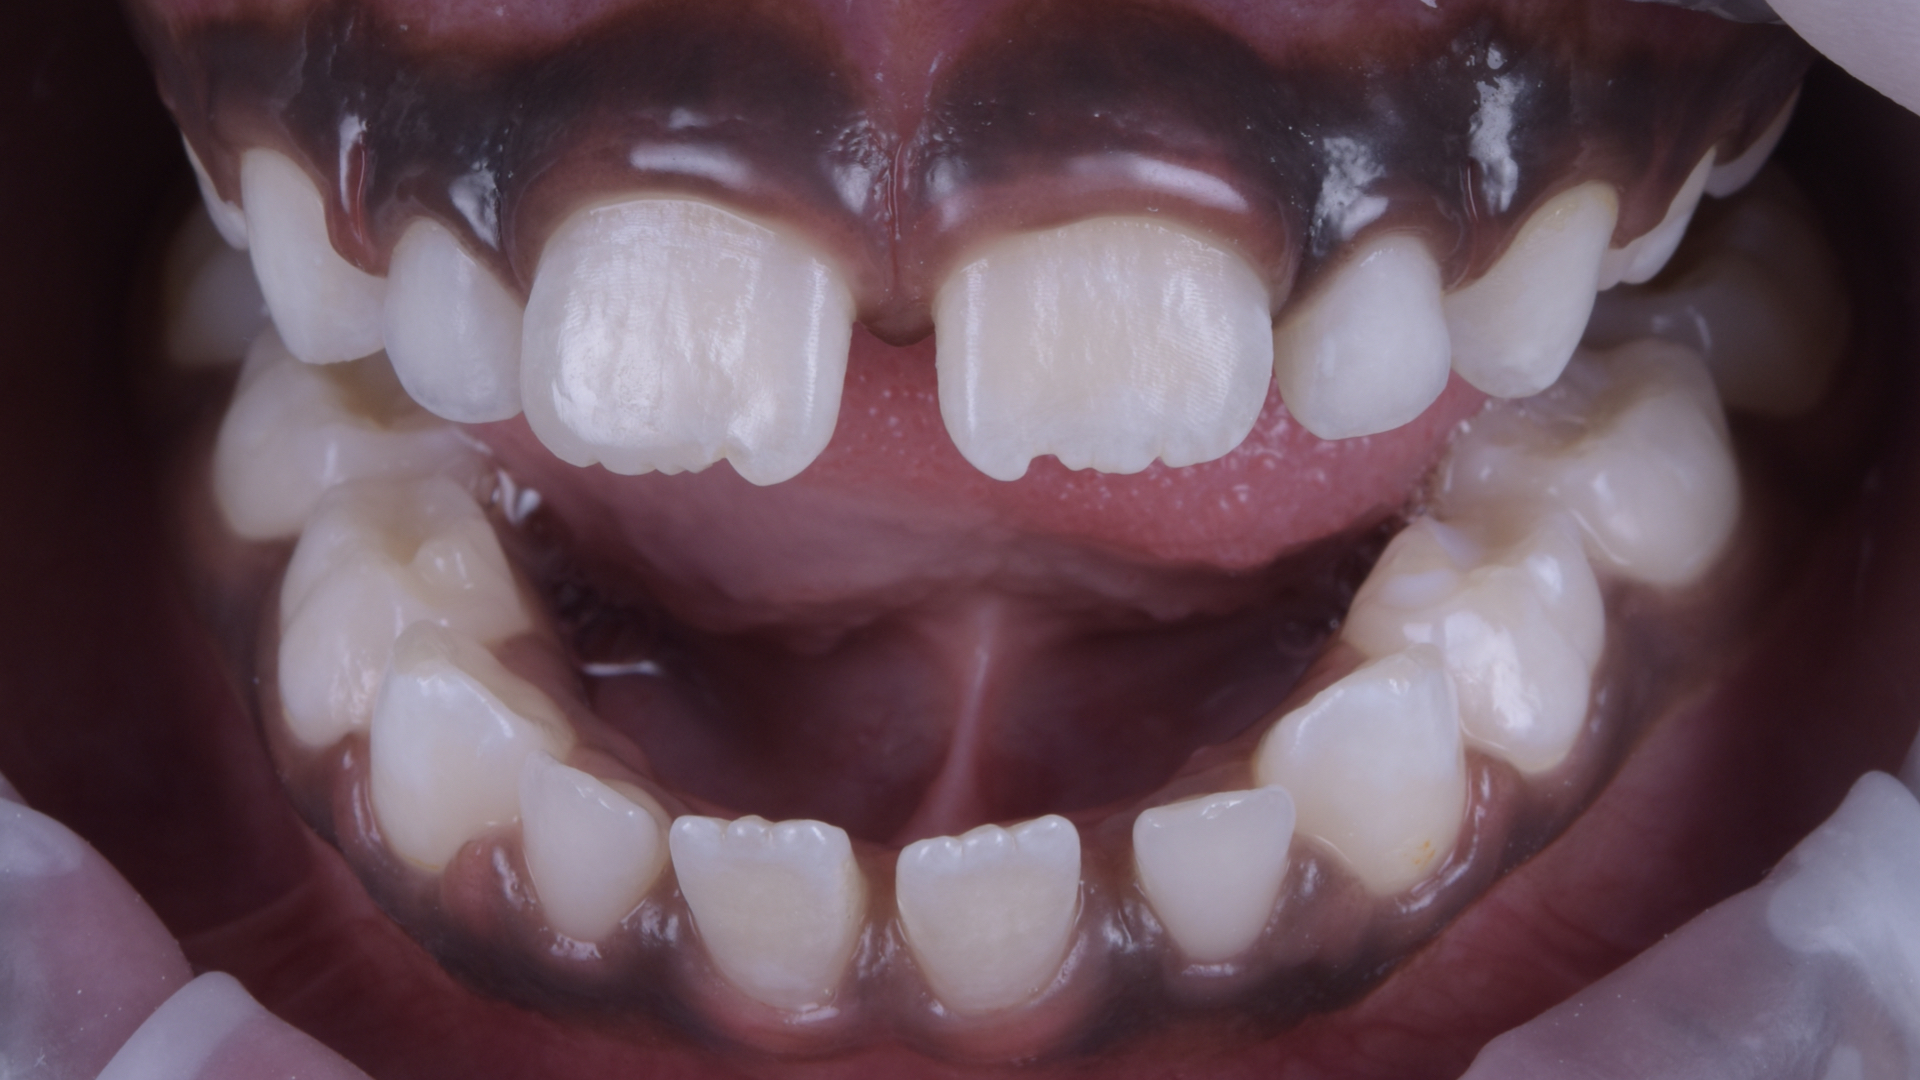

Ein sechsjähriges Mädchen, das sich guter Gesundheit erfreute, stellte sich mit ihrer Mutter in der Praxis vor. Ihr Hauptanliegen war die Versorgung der frakturierten Inzisalkante des Zahnes 11. Aufgetreten war die Fraktur im Rahmen eines Unfalls in der Schule. Bei der klinischen Untersuchung zeigte sich eine Schmelzfraktur an der Schneidekante sowie dem distalen Rand des Zahnes 11. Gemeinsam mit der Mutter wurde entschieden, die Form, Kontur und Ästhetik des Zahnes mit Komposit wiederherzustellen. Die Komposit-Versorgung wurde freihändig hergestellt – anstelle eines palatinalen Silikonschlüssels wurde zur Stabilisierung ein Finger verwendet (sog. Finger Index Technique). Zur Wiederherstellung der Form, Kontur und Ästhetik kam 3M Filtek Easy Match Universal Restorative im Farbton Bright zum Einsatz. Die Formgebung im Bereich der Inzisalkante erfolgte mit feinkörnigen rotierenden Instrumenten. Die Materialien der Wahl für die finale Oberflächenpolitur waren 3M Sof-Lex Ausarbeitungs- und Polierscheiben, Bimssteinpaste und Polierpaste.

Ansicht von lateral.